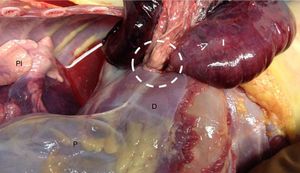

Se presenta el caso de un niño de 13 meses sin antecedentes médicos, que llega al centro de salud en situación de parada cardiorrespiratoria y fallece tras maniobras de RCP avanzadas. Había sido visitado en el mismo centro 5h antes por cuadro de dolor abdominal con 2 episodios de vómito alimenticio y febrícula (37,4°C). Desarrollo estaturo-ponderal adecuado, externamente no se hallaron lesiones ni otros hallazgos relevantes. El examen interno reveló en hemitórax izquierdo un derrame pleural serohemático y la presencia de una amplia porción intestinal de aspecto necrótico-hemorrágico con desplazamiento de estructuras mediastínicas (fig. 1). Se identificó orificio localizado en la porción posterolateral izquierda del diafragma, a través del cual se había producido la herniación (fig. 2). No se hallaron otras malformaciones congénitas. El estudio toxicológico fue negativo y el estudio histopatológico informó también de un cierto grado de colapso pulmonar izquierdo y signos de aspiración alimentaria terminal difusa. La presentación tardía (después del primer año) de la HDC como causa de muerte súbita es excepcional.